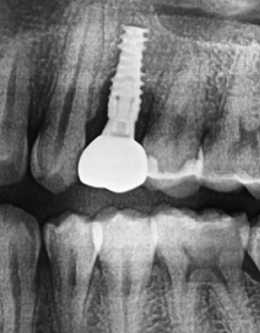

Peri-Implantitis Rescue

Implant #12

Challenge: Patient presented with severe peri-implantitis on implant #12, exhibiting 50% radiographic bone loss, deep pockets, and inflammation.

Solution: Laser-assisted surface decontamination and regenerative bone grafting to salvage the fixture without explantation.

Outcome: 100% radiographic bone regeneration achieved with complete resolution of inflammation and stable soft tissue attachment.

Peri-Implantitis regeneration & salvage